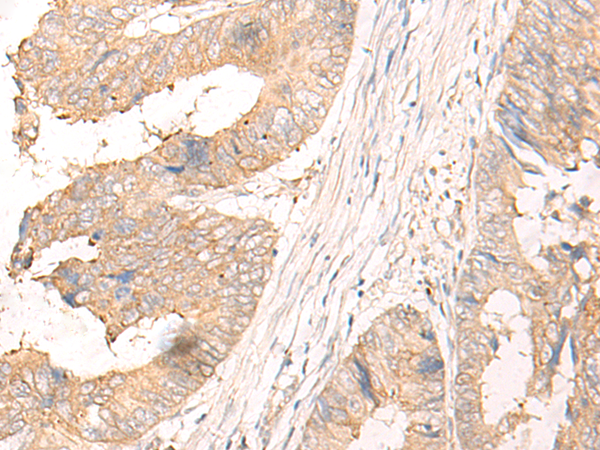

分类: 科研抗体货号: P06483别名: Cipp; INADL; hINADL; InaD-like应用: IHC反应种属: Human

分类: 科研抗体货号: P06482别名: GBAS应用: WB,IHC反应种属: Human, Mouse